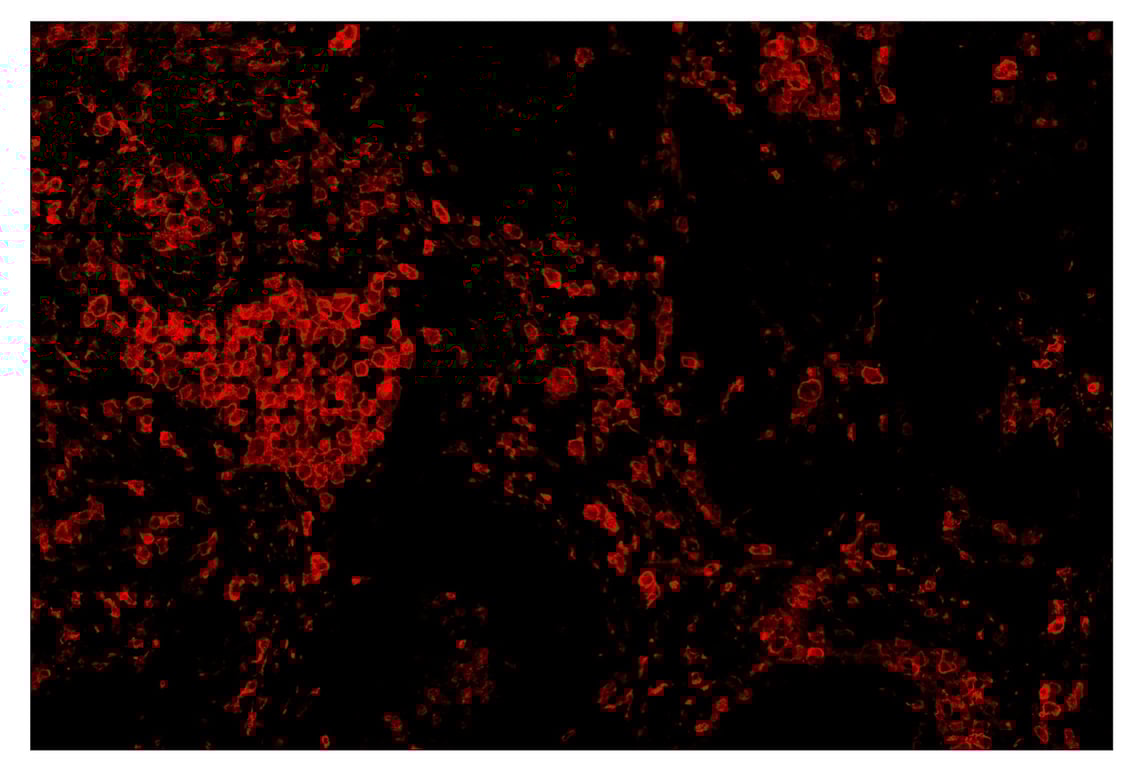

SignalStar™ immunohistochemical analysis of paraffin-embedded human squamous cell lung carcinoma using CD163 (D6U1J) & CO-0022-647 SignalStar™ Oligo-Antibody Pair #57183 (red). All fluorophores have been assigned a pseudocolor, as indicated. Staining was performed on the BOND RX by Leica Biosystems.

Immunohistochemistry Image 4: CD163 (D6U1J) & CO-0022-594 SignalStar<sup>™</sup> Oligo-Antibody Pair